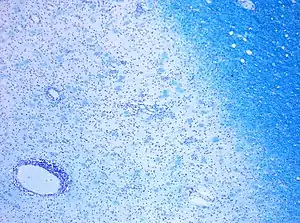

CD68-stained tissue shows several macrophages in the area of a demyelinated lesion caused by MS.

Demyelination in MS: On Klüver-Barrera myelin staining, decoloration in the area of the lesion can be appreciated.